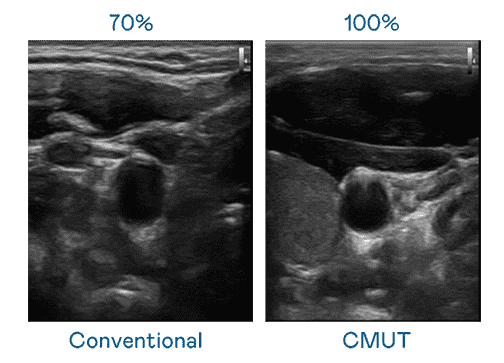

CMUT 技术是一种用电容式微机电元件来产生超音波讯号的技术。。。与传统 PZT 压电式技术相比,,,,CMUT 频宽增加 30%,,更宽频的超音波讯号让影像解析度大幅提升,,是实现高影像品质医疗超音波扫描、、、促进精准医疗发展的关键技术。。。。

大频宽带来超清晰影像

超音波影像的解析度高低,,,首先取决于探头能发出的讯号频宽。。。彩运网 CMUT 可提供高清晰的超音波讯号,,提供高频宽、、、、高灵敏度、、、影像纹理细节更高的超音波影像,,,,协助医护人员缩短影像判读时间及利用精准的医疗影像进行诊断。。。。